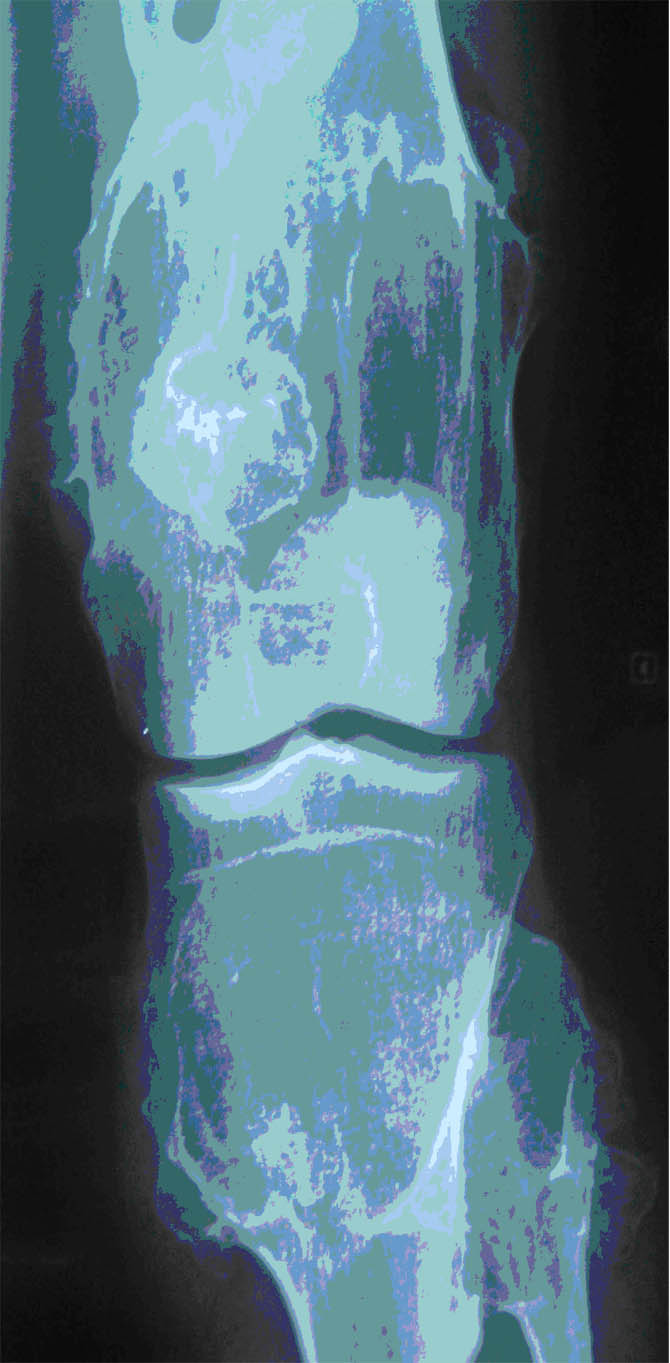

Maladie Polyexostosante du genou